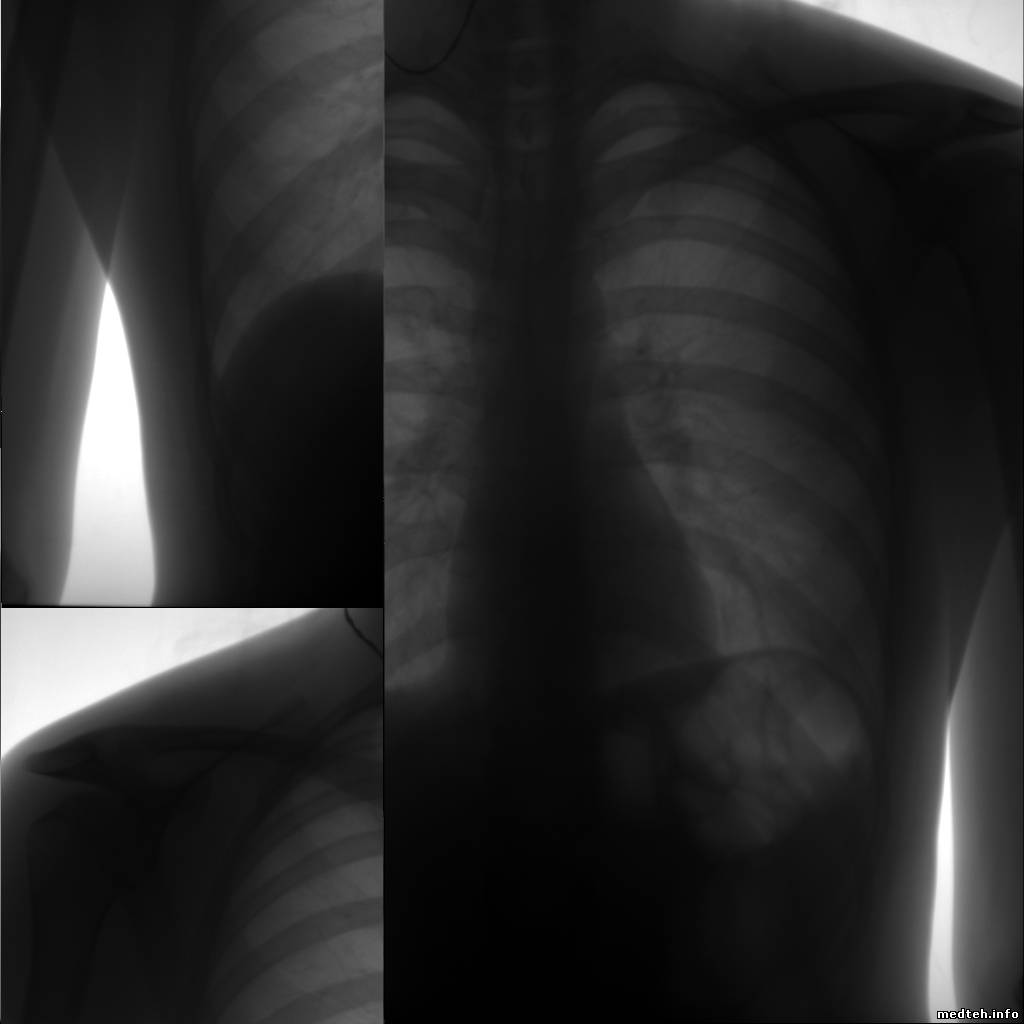

| Форум медтехников Медицинское оборудование (тех. разделы) Рентгеновское оборудование. Цифровой флюорограф "12ФК1" с камерой "Пони" (Иногда рвет снимки) |

| Цифровой флюорограф "12ФК1" с камерой "Пони" | |||||||||